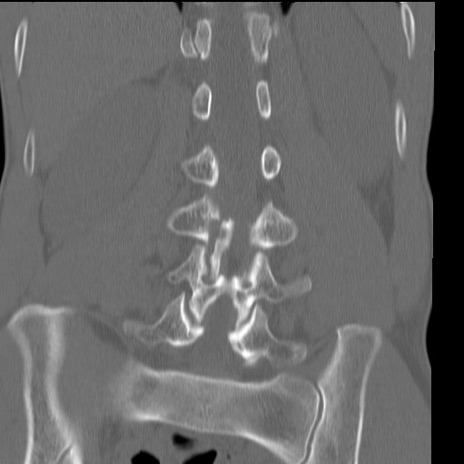

症例3 腰椎CT(冠状断像)

腰椎CT

横断像